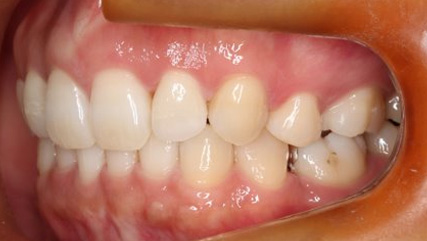

上顎前突といわれ、上顎の前歯が唇側に出ている状態を言います。

前歯が出ることで見た目の問題もありますが、口を閉じることができない、口呼吸をしてしまう、外傷などのリスクがあります。

日本人に叢生の次に多い不正咬合と言われており、自然に治ることはありません。また上の前歯が出ている事だけが気になるかもしれませんが、多くの場合、上顎の奥歯の位置に問題があることが多く、部分矯正でなく根本的な治療をした方がいい場合が殆どです。

口を閉じることができないことで、鼻呼吸でなく口呼吸をしてしまい、結果、成長期の場合顎の骨の成長を邪魔してしまうとも言われております。その他、口呼吸はアトピーなどを含むアレルギー症状の悪化、風邪を含むウイルス性の感染症にかかりやすいなどのリスクも増大してしまいます。

歯並びだけでなく全身への影響も多い為、早期の治療をおすすめ致します。